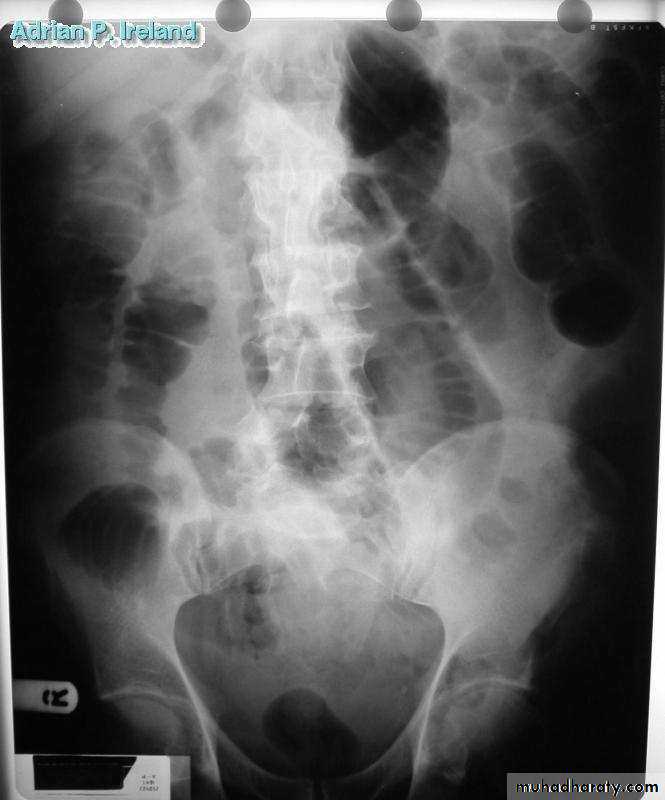

• Radiology; PFA, Large bowel obstruction

• Radiology; CT, Large bowel obstruction

• Operative Findings; Large bowel obstruction